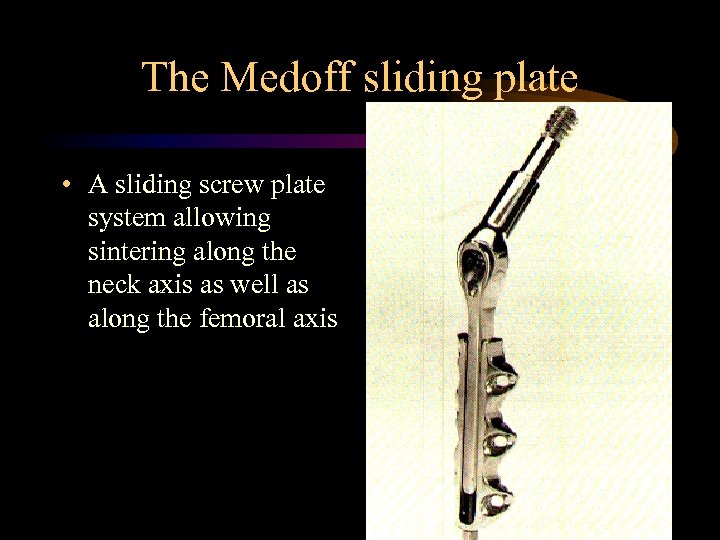

The Medoff sliding plate • A sliding screw plate system allowing sintering along the neck axis as well as along the femoral axis

The Medoff sliding plate • A sliding screw plate system allowing sintering along the neck axis as well as along the femoral axis